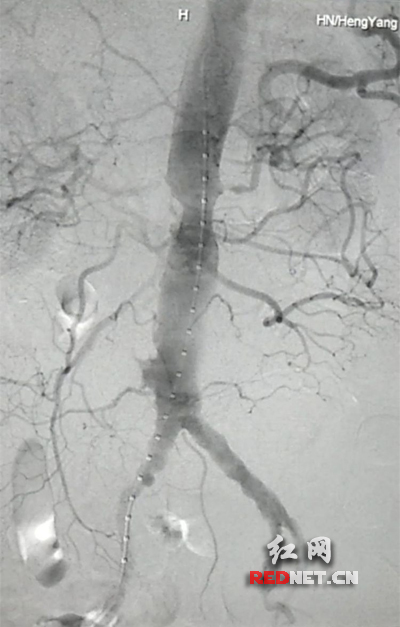

血管介入科行腹主动脉瘤覆膜支架隔绝术(“裤衩”支架植入)。

患者因腹部搏动性肿块行成已有4年,伴右下腹疼痛6小时入院,既往有高血压病史,患者入院后血压较高,医护人员随即予以控制血压、止痛处理,经检查提示患者有肾下腹主动脉瘤,合并心、肝、肺、肾等重要脏器疾患,根据 Laplace定律,动脉瘤直径越大压力越大,老人动脉脆弱,动脉瘤随时有破裂的可能性,其危险性大。血管介入科排除各种困难,在麻醉科协作下行腹主动脉瘤覆膜支架隔绝术(“裤衩”支架植入),手术持续了1个半小时,患者术后安返病房,麻醉醒后露出了微笑,向医务人员伸出大拇指。